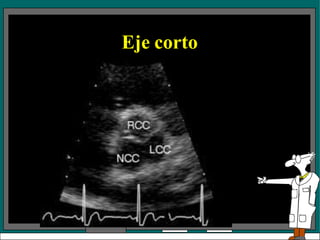

• A nivel de la válvula aortica se puede

observar: Aorta, AI, AD, VD, Válvula

aórtica, con sus tres cúspides (derecha ,

izquierda y no coronariana), válvula

pulmonar, válvula tricuspidea, septum IA,

tronco de la arteria coronaria izquierda

• Permite identificar también el apéndice de

la aurícula izquierda